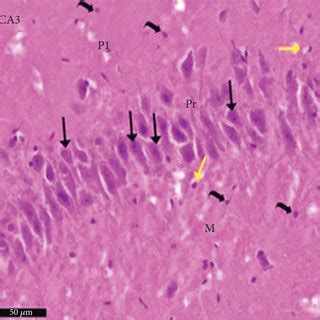

• Photomicrograph Of The CA1, CA3, And DG Regions Of The Hippocampus Of A ...

• Photomicrograph Of Brain Hippocampus (CA3 And CA1 Areas) Sections ...